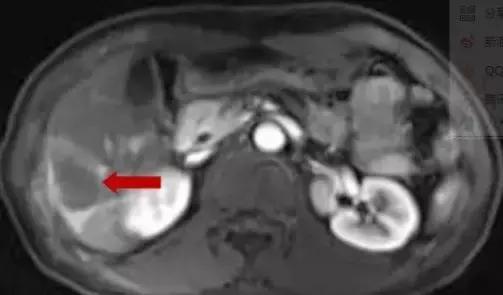

术前MDT讨论,拟行超声引导下肝转移瘤射频消融术+腹腔镜下右半结肠癌根治术。在超声引导下肝转移射频消融术前讨论,考虑肝内转移病灶临近肝包膜下,病灶边缘可见肝右静脉及其分支环绕,拟行双针多点重叠消融,术中遵循消融范围至少≥癌周1cm,先深后浅原则,先沿肝静脉布针,两针间距不超过2cm。

布针及射频消融